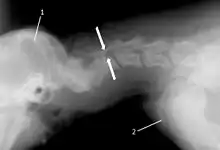

The disease tends to be gradually progressive. Symptoms such as weakness, ataxia, and dragging of the toes start in the rear legs. Dogs often have a crouching stance with a downward flexed neck. The disease progresses to the front legs, but the symptoms are less severe. Neck pain is sometimes seen. Symptoms are usually gradual in onset, but may progress rapidly following trauma.[6] X-rays may show misaligned vertebrae and narrow disk spaces, but it is not as effective as a myelogram, which reveals stenosis of the vertebral canal. Magnetic resonance imaging has been shown to be more effective at showing the location, nature, and severity of spinal cord compression than a myelogram.[7] Treatment is either medical to control the symptoms, usually with corticosteroids and cage rest, or surgical to correct the spinal cord compression. The prognosis is guarded in either case. Surgery may fully correct the problem, but it is technically difficult and relapses may occur. Types of surgery include ventral decompression of the spinal cord (ventral slot technique), dorsal decompression, and vertebral stabilization.[8] One study showed no significant advantage to any of the common spinal cord decompression procedures.[9] Another study showed that electroacupuncture may be a successful treatment for Wobbler disease.[10] A new surgical treatment using a proprietary medical device has been developed for dogs with disc-associated wobbler disease. It implants an artificial disc (cervical arthroplasty) in place of the affected disc space.[11]

Wobbler disease is definitively diagnosed by x-ray, nuclear scintography or bone scan. X-rays will show channel widening or filling the easiest and are often most cost effective to horse owners. X-rays will also show any structural anomaly, arthritis, facet remodeling, or bone spurs present. Preliminary diagnosis can be made by ultrasound but x-rays are needed to measure the true depth of facet involvement. For extent of damage to associated structures, veterinarians may opt to have the horse undergo a bone scan or nuclear scintography.